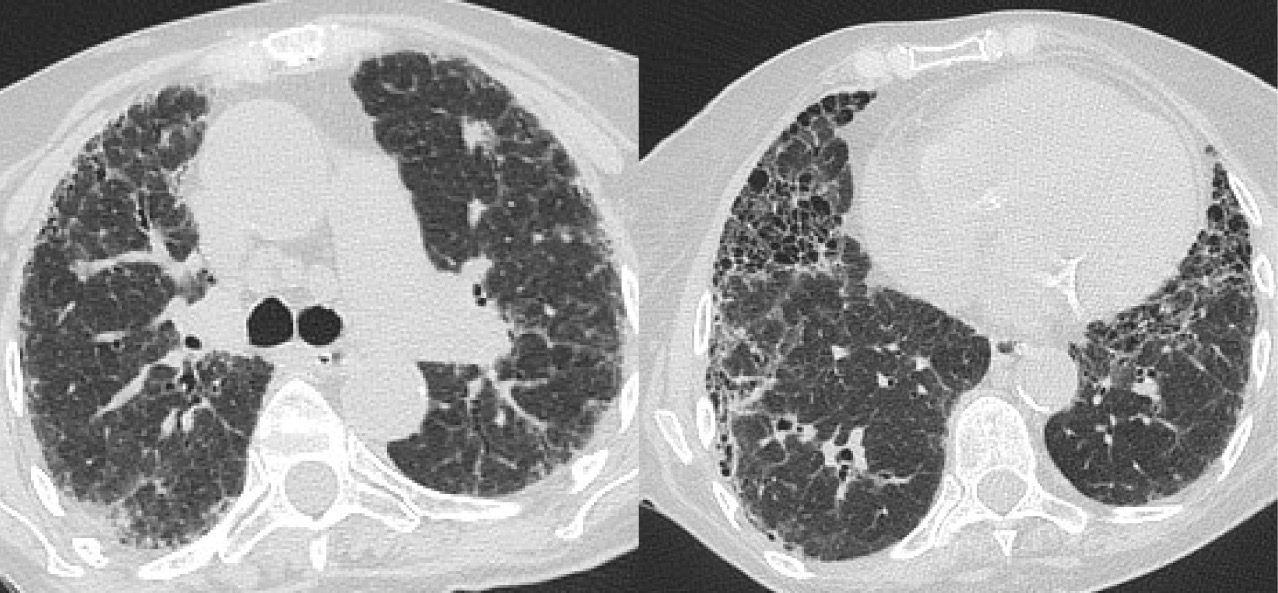

Ухудшение состояния отмечено с 2017 г., когда появилась одышка при умеренных физических нагрузках, сухой кашель. Была госпитализирована в пульмонологическое отделение. В анализах крови: лейкоциты 8,5 × 109/л, СОЭ 28 мм/ч, СРБ 11 мг/л; ферритин 25 мкг/л, щелочная фосфатаза (ЩФ) 855 Ед/л, аспартатаминотрансфераза 69 Ед/л, аланинаминотрансфераза 59 Ед/л, общий билирубин 30,2 мкмоль/л, прямой билирубин 27,3 мкмоль/л. Повышение уровней лактатдегидрогеназы, креатинфосфокиназы, РФ, антител к нативной ДНК, ANA, ACPA, ANCA, антител к миелопероксидазе, протеиназе, антигенам Scl-70, Jo-1, антител к микросомальной фракции печени и почек, антимитохондриальных антител, криоглобулинов и иммуноглобулинов (Ig) A, M, G не выявлено. При проведении ультразвукового исследования органов брюшной полости обнаружена умеренная спленомегалия (14 × 10 × 9 см), диффузные изменения печени, признаки хронического калькулезного холецистита. Бодиплетизмография: жизненная емкость легких (ЖЕЛ) 65%, ФЖЕЛ 69%, ОФВ1/ФЖЕЛ 70%; общая емкость легких 68%, остаточный объем легких 63%, DLCO 53%. Бронхоскопия выявила эрозивный бронхит, трансбронхиальная биопсия – признаки эндобронхита. При компьютерной томографии (КТ) ОГК наблюдались зоны «матового стекла», диффузные пневмосклеротические изменения в плащевых зонах обоих легких (рис. 1).

Рис. 1. Компьютерная томография органов грудной клетки: аксиальные срезы. Двусторонние распространенные зоны «матового стекла» с ретикулярными интерстициальными изменениями, утолщение стенок бронхов